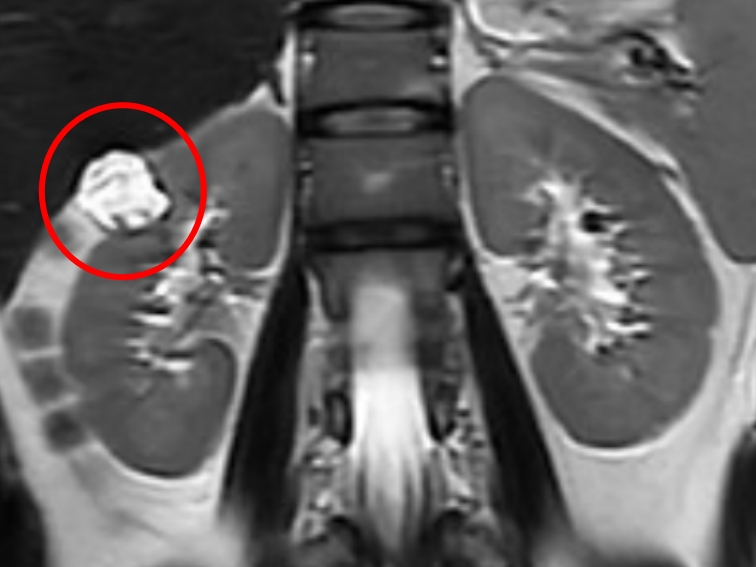

△增强MRI检查发现李女士有右肾占位性病变,且恶性肿瘤的可能性极大

为进一步的治疗,省二医民航院区健康管理(体检)科的医生立即联系了泌尿外科负责人、副主任医师刘百川。在专科医生的建议下,李女士接受了增强MRI检查,结果显示其右肾占位性病变为恶性肿瘤的可能性极大。刘百川副主任医师介绍道:“结合目前的检查结果,李女士所患的肾肿瘤可能为局限性肾癌。对于局限性肾癌,早期手术是主要的治疗手段,可显著提高患者的生存率。如果不尽早处理,肾肿瘤可能会发生进展并出现远处转移。”